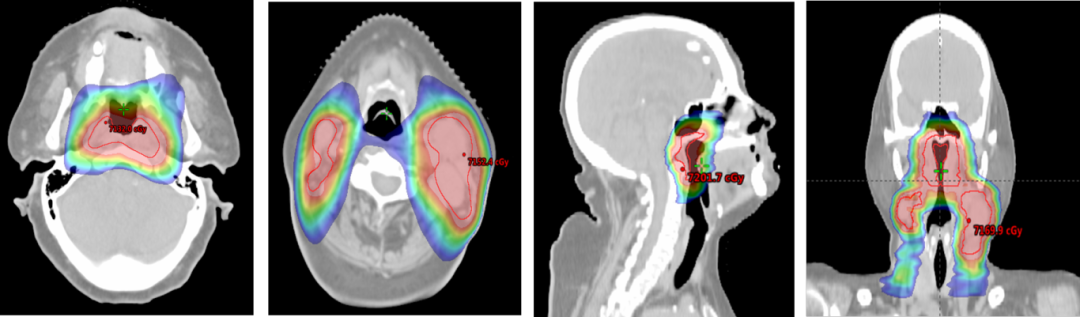

放疗(2024126日起)

GTVp68Gy/31F,GTVnd-L 68Gy/31F, GTVnd-R 66Gy/31F,PTV1 61Gy/31F,PTV2 55Gy/31F因淋巴结消退明显,10次后重新再定位,15次后以新计划继续放疗。放疗过程中出现2级放射性咽喉炎、放射性皮炎。